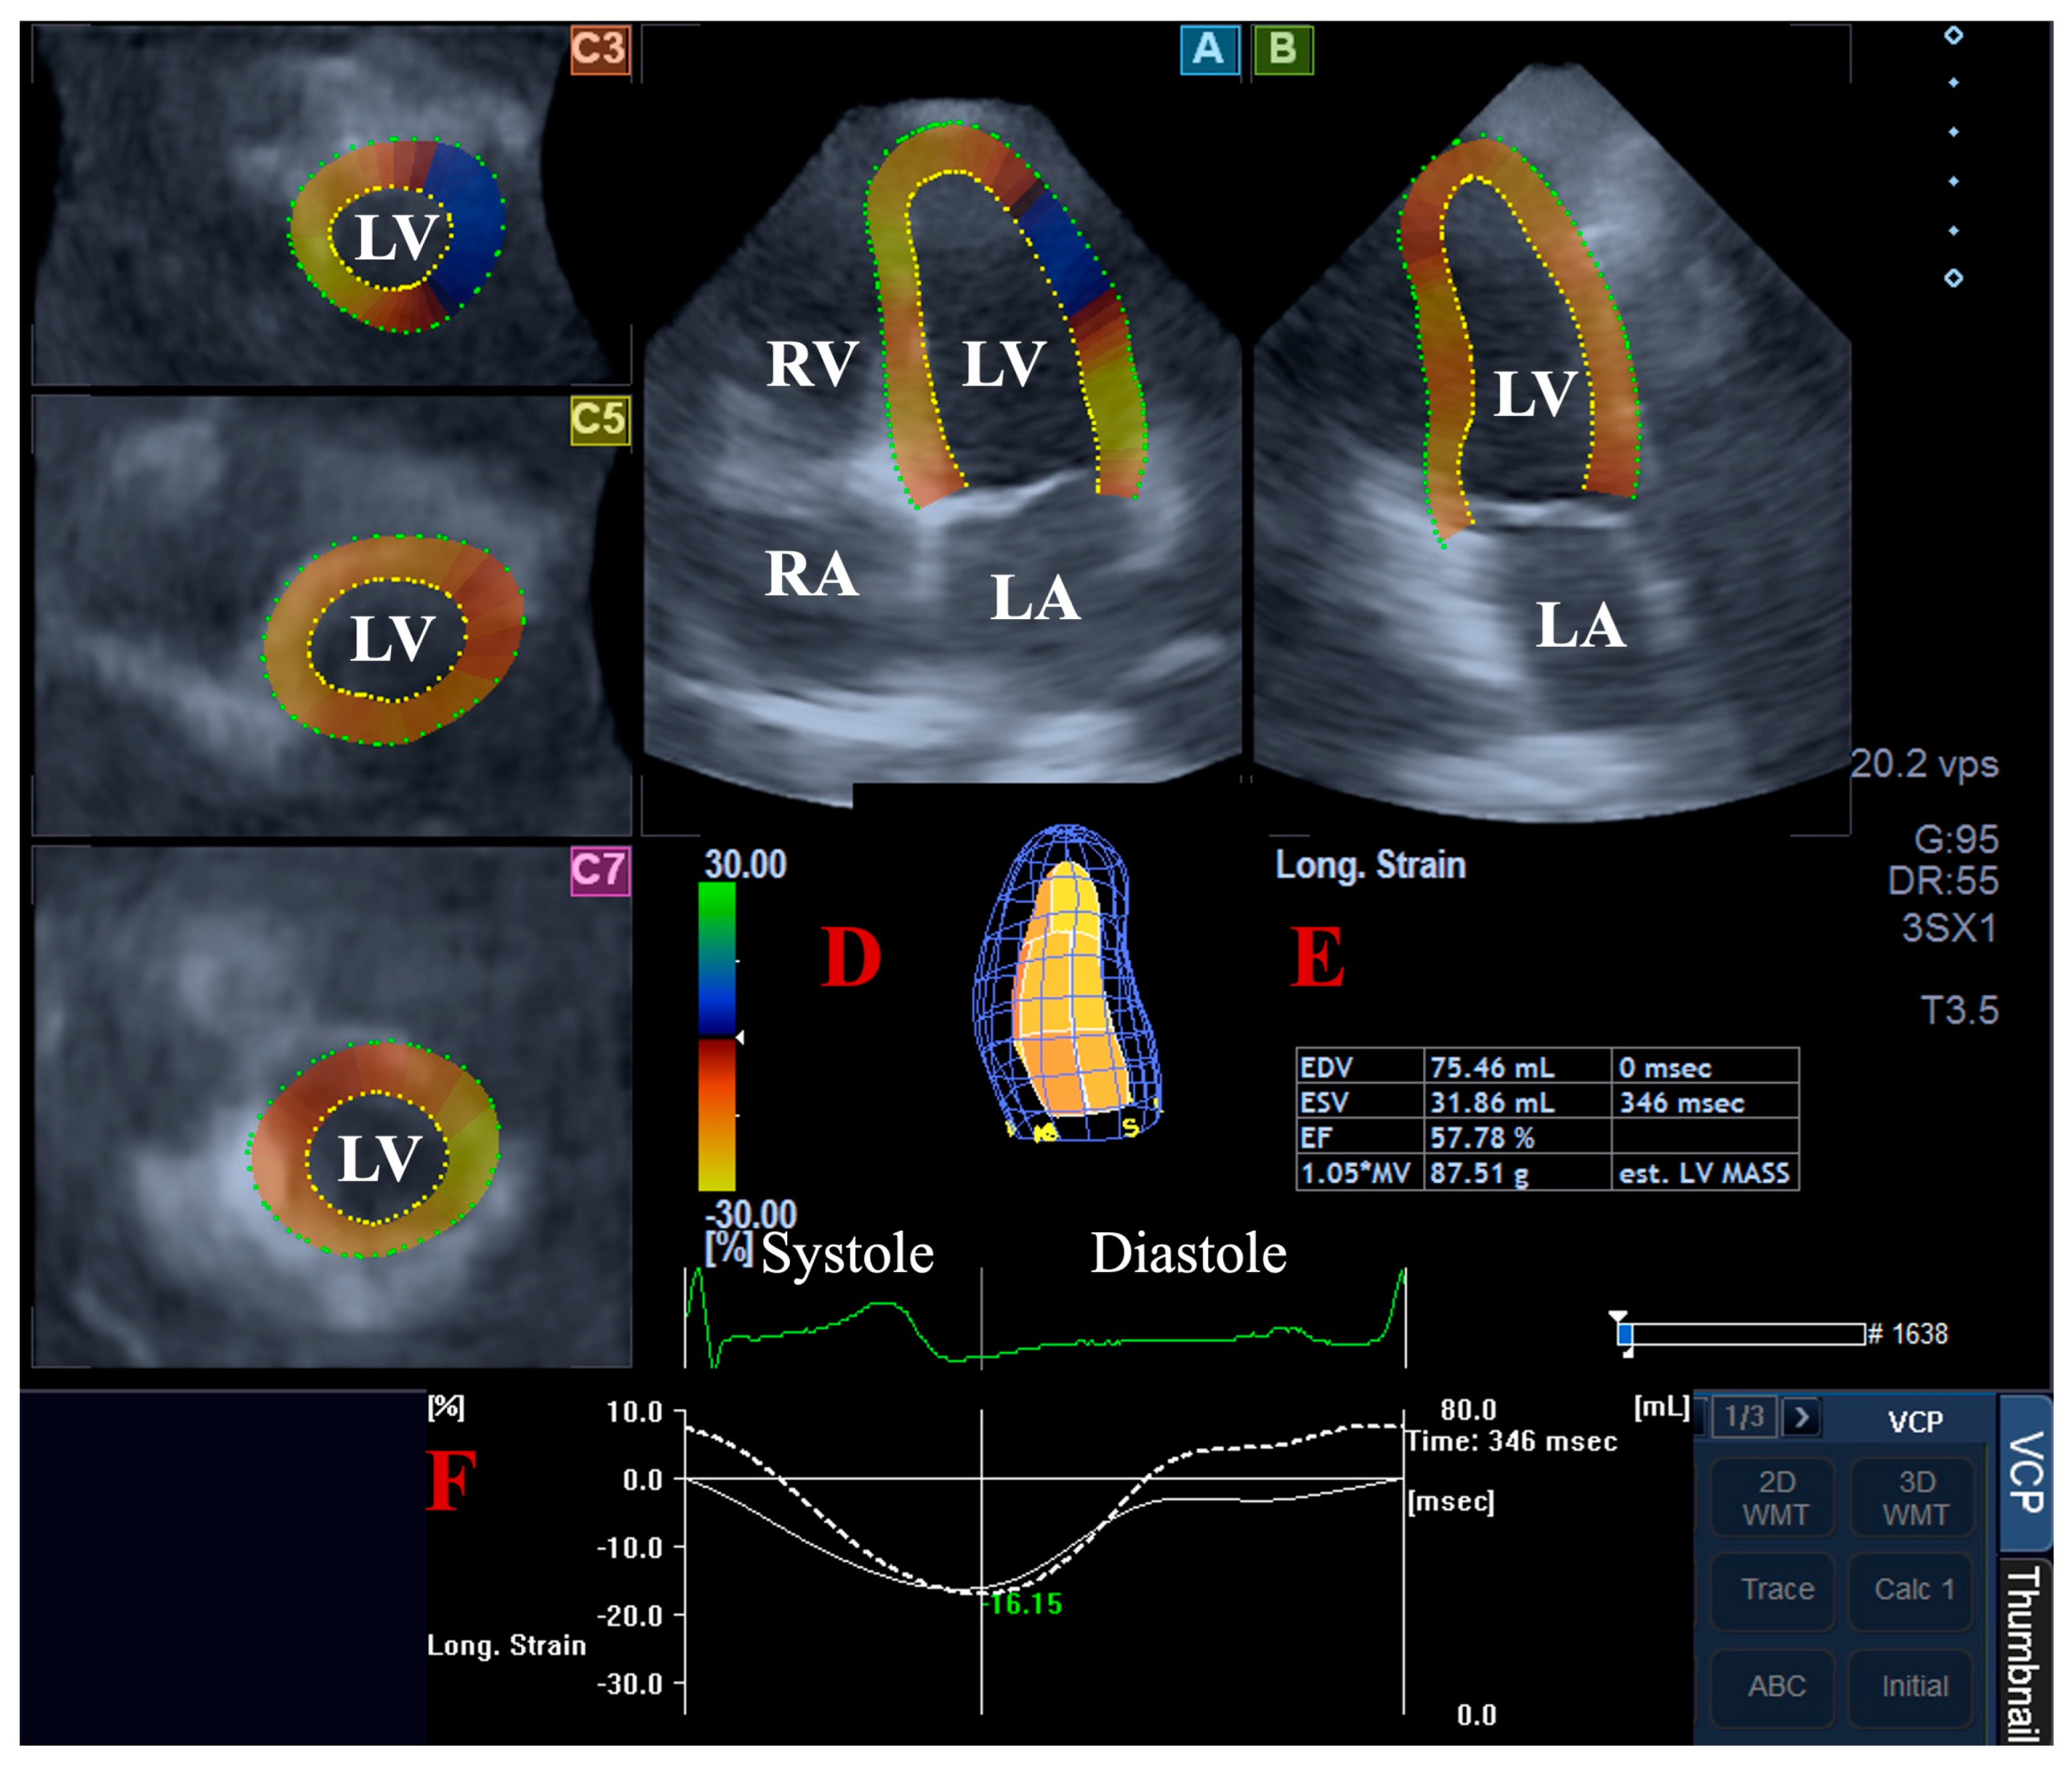

For the LV volumetric assessments, the data were presented in apical long-axis four-chamber (AP4CH) and two-chamber (AP2CH) views and three (basal, midventricular, and apical) cross-sectional views, which were automatically created by the software. Following plane optimalisations and definitions of the mitral annulus—LV septal and lateral edges and the LV apical endocardial surface by the observer—a sequential analysis was performed with automatic contour detection; then, a virtual 3D model of the LV was created together with LV volumetric data with respect to the cardiac cycle [2,4,5,6,7] (Figure 1).

Figure 1.

Volumetric assessment of the left ventricle (LV) by three-dimensional (3D) speckle-tracking echocardiography: apical four-chamber (A) and two-chamber long-axis views (B) and short-axis views at basal (C3), midventricular (C5), and apical LV levels (C7) are shown together with a virtual 3D model of the LV (D) and calculated LV volumes (E). Time—global LV circumferential strain curve (white line) and time—LV volume changes curve (dashed white line) are demonstrated as well (F). Abbreviations: LA, left atrium; LV, left ventricle; RA, right atrium; RV, right ventricle; EDV, end-diastolic volume; ESV, end-systolic volume; EF, ejection fraction.